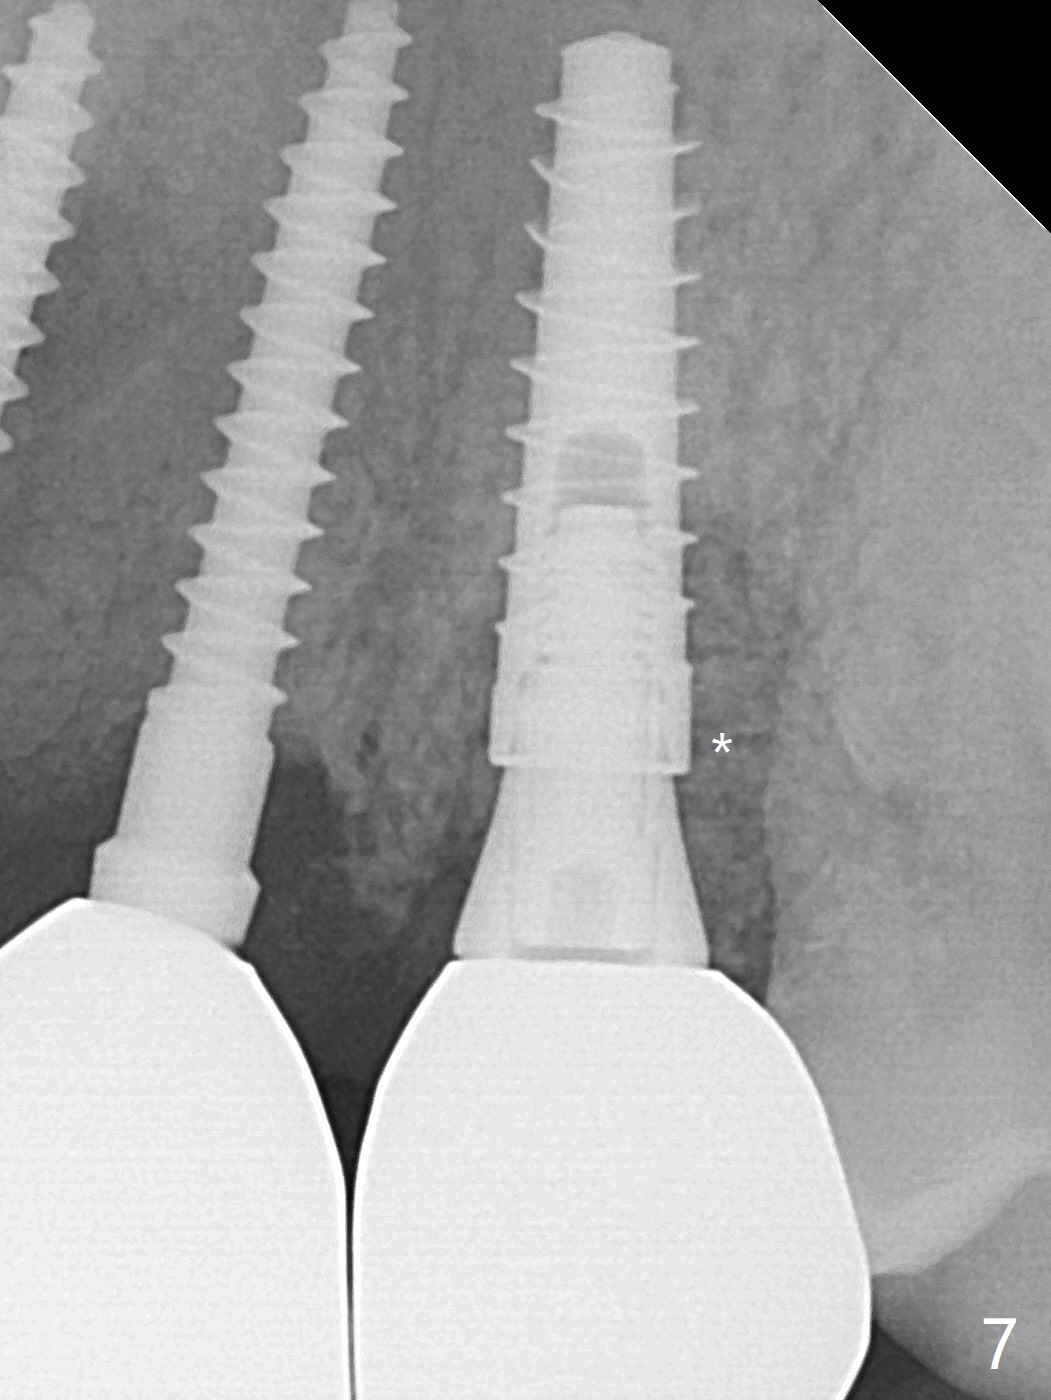

There is no obvious black triangle between the implants at #8-11 (Fig.1 post infiltration). Following papilla (Fig.2 *) sparing incision and elevation of the buccal flap, the fenetration of the buccal plate around the socket shield (Fig.3 S) is found at #11; there is a distal defect with granulation tissue (*). After shield and granulation tissue removal, the coronal implant is found exposed (Fig.4 until osteotomy). The relatively flat surface of IBS implant is apparently less likely to develop periimplantitis. With periosteal relief and placement of sticky bone (Fig.7 *), PRF and 6-month membrane, the wound is closed with 4-0 PTFE suture (Fig.5). Failure of socket shield is related to retention of the apex (Fig.6 <). Probe before extraction and remove apex and gutta percha. There appears no buccal or palatal (P) defect 9 months post shield removal (17 months post cementation, Fig.8), although the bone density palatally is low. Although the sagittal section (Fig.9 (lower left panel) shows the absent palatal plate at #10, the 3-D image and the coronal section do not (upper let and right panels). The 2.5 mm implant at #9 appears to have been placed buccal (Fig.10 B), although the buccal crest is present. In contrast the 2.5 mm implant at #8 appears within the bone boundary (Fig.11). The soft tissue remains healthy at #8-11. Bone graft will be done if needed.